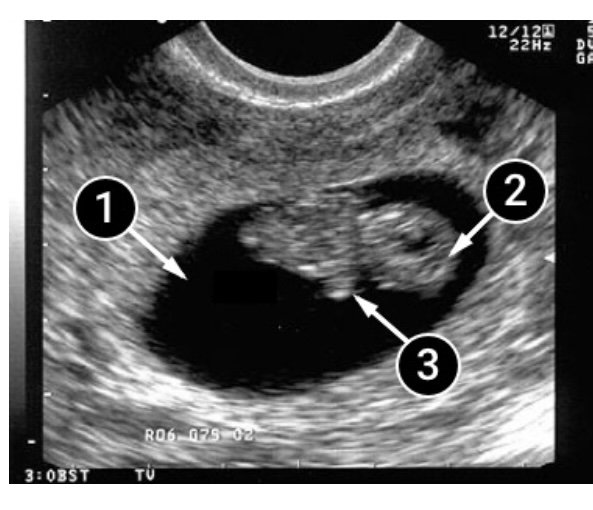

¿Qué se puede ver en la ecografía/ultrasonido?

En la ecografía, ya podemos ver cuando el bebé está durmiendo, y cuando está despierto,

puesto que en esta semana exhibe actividad motora, lo que significa que se mueve mucho, brazos, piernas, da saltitos y se gira!

En la primera imagen, se ve claramente un gran óvalo oscuro: una bolsa fetal con un bebé. Estas imágenes son de ecografía 2D, pero en el centro os mostraremos al bebé en ecografía 5D y os explicaremos muy detalladamente en movimiento y en tiempo real que es lo que estamos viendo!

Presta atención a su postura, el bebé se acuesta de espaldas a la pared frontal del útero y se puede apreciar que la espalda del bebé ya está enderezada.

En la etapa actual del embarazo, el sistema óseo del bebé se fortalece y se desarrolla el sistema músculo esquelético. El bebé ya puede doblar los codos, como se puede ver en la imagen, en la cual las pequeñas manitas se encuentran recogidas contra su pecho. Las extremidades superiores aún crecen más rápido que las inferiores.

La cabeza es claramente visible en la imagen. Ahora la cabeza del bebé comienza a redondearse, adquiriendo una forma mas redondita.

- Saco amniótico.

- Cabeza del bebé.

- Bracito.